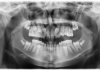

Il laser erbio in chirurgia ossea orale Premium

Il laser erbio è uno strumento versatile, che offre un'ampia possibilità terapeutica con l'applicazione sui tessuti duri e molli. A livello ambulatoriale può essere utilizzato per trattare diverse condizioni cliniche e come alternativa efficace agli strumenti meccanici tradizionali per eseguire interventi di chirurgia orale, offrendo precisione con ridotto danno termico e rapidità di guarigione. Gli autori presentano quattro casi clinici dove il successo terapeutico è stato ottenuto grazie all'impiego del laser erbio.